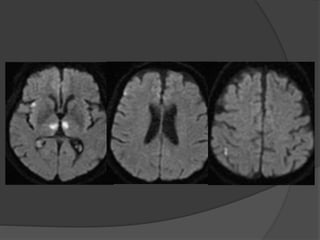

Case 2: 41M, AMS, s/p

seizure

Courtesy: Matt Fox, MD

Feb 2014June 2014

DWI FLAIR

T2 T1

T2 ADC

ADC

DWI

Patchy restriction of diffusion in a

cortical distribution (but not in all

areas of edema)

Case 2 Diagnosis: MELAS

 MELAS (mitochondrial encephalopathy with lactic

acidosis and stroke-like episodes

 Characterized by 'stroke-like' episodes, typically in

childhood or early adulthood (90% present before 40

years of age)

 Encephalopathy, seizures, dementia, lactic acidosis ,

muscle weakness

 CT: Atrophy, multiple infarcts involving multiple vascular

territories. Parieto-occipital and parieto-temporal

involvement is most common, basal ganglial calcification

• MRI: Swollen gyri with increased T2 signal, increased

signal on DWI (T2 shine through) with no change on ADC

indicating vasogenic edema

• MR spectroscopy: Elevated lactate